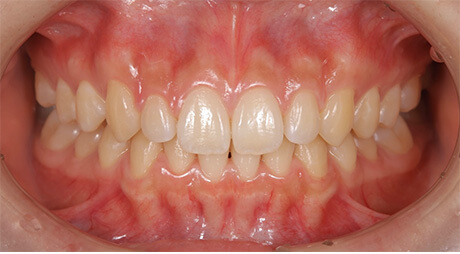

上の前歯の古い被せ物を治したいと言うことで来院されました。上下の前歯は少しガタガタになっており、奥歯には古い金属の詰め物が見られます。

上の前歯の被せ物が長い期間保つようにするためには、下の前歯のガタガタを整えておく必要があります。この症例くらいのガタガタであれば、インビザラインGoを使えば短期間で綺麗に治すことができます。歯並びが整ったことで治療のモチベーションが上がり、ホワイトニングと奥歯の銀歯を全てセラミックに置き換える治療を行い、金属がない(ノンメタル)状態になりました。